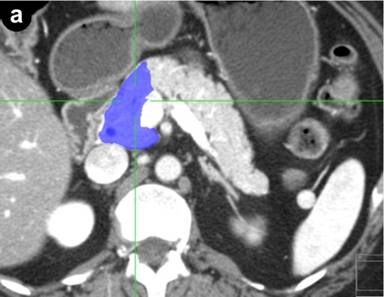

Preoperative computed tomography or magnetic resonance imaging were analyzed by the same radiologist who was blinded to the postoperative course. The volume of the pancreatic remnant was measured using a Voxar® 3D workstation (Barco NV, Kortrijk, Belgium) with 3D segmentation and volume calculation (Figures 1 and 2). The length and width of the resection plane were measured. The caliber of the main pancreatic duct was measured in the resection plane and in the head of the pancreas, as was the distance of the resection margin from the lesion.

Figure 1. Computed tomography of the pancreas. 3D volume rendering image of the pancreas with the remaining pancreas shown in blue. |

Figure 2. Computed tomography of the pancreas showing 3D segmentation and volume calculation of the pancreatic remnant (in blue) in transverse (a.), coronal (b.), and sagittal (c.) images. |